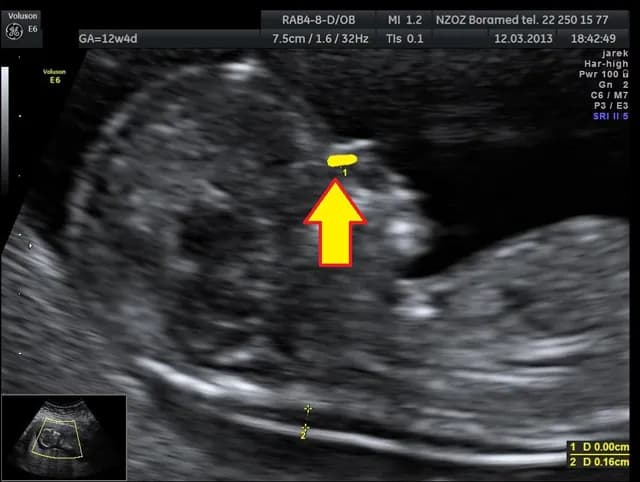

Czy na USG można wykryć zespół Downa? Kluczowe informacje i wskazówki

Czy na USG można wykryć zespół Downa? Dowiedz się, jakie cechy mogą wskazywać na ryzyko i jakie badania warto rozważyć w ciąży.